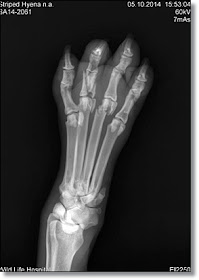

Finally, the rest of the hyena’s test results were back. The X-rays showed extensive broken bones throughout the creature’s body. He had very clearly been badly beaten, either during his capture or during his time in captivity.

The worst of his injuries was a badly broken front leg and paw. The veterinarian treating the hyena said that the break looked as though he had gotten his paw caught in a massive trap; if this was true, it would make sense, seeing as that’s mostly likely the easiest way his captors would’ve been able to apprehend him.